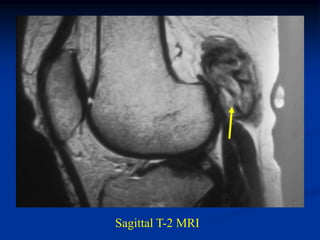

Case #253

29 year male

recent fracture ulna

18 months later

with desmoid tumor

at fracture site

Sagittal T-2 MRI 18 months later with desmoid tumor

Case #253 29 yearmale recent fracture ulna

18 months later withdesmoid tumor at fracture site

Sagittal T-2 MRI18 months later with desmoid tumor